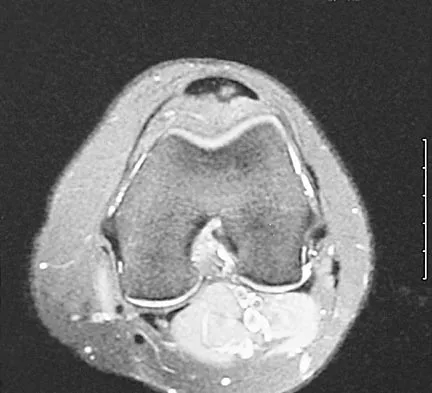

Figure 22 shows the MRI scan of a 20-year-old female basketball player who has pain over the anterior knee that interferes with her performance. Examination reveals phase III Blazina patellar tendinosis. Management should consist of

Explanation

Excision of the affected mucoid degenerative area is considered appropriate management in the Blazina classification system. A finding of phase III indicates persistent pain with or without activities, as well as deterioration of performance. With the appearance of the mucoid degeneration and the vigorous activity level of the intercollegiate basketball player, it is unlikely that nonsurgical management will provide adequate relief. When excising the affected degenerative area, care must be taken to retain normal tendon fibers. The defect in the patellar tendon is closed with absorbable sutures, as is the paratenon. Postoperative rehabilitation involves initial mobilization extension, with progressive range-of-motion and mobilization exercises as tolerated and weight bearing as tolerated. Open chain and isokinetic exercises are delayed until full range of motion and mobility is obtained, generally within 4 weeks. A return to activities is achieved by 80% to 90% of athletes, although there may be occasional activity-related aching for 4 to 6 months after surgery. Blazina ME, et al: Jumper's knee. Orthop Clin North Am 1973;4:665. Kelly DW, Carter VS, Jobe FW, Kerlan RK: Patellar and quadriceps tendon ruptures: Jumper's knee. Am J Sports Med 1984;12:375-380. Krums PE, Ryder B: Operative treatment of patella tendon disorders. Operative Techniques Sports Med 1994;2:303.